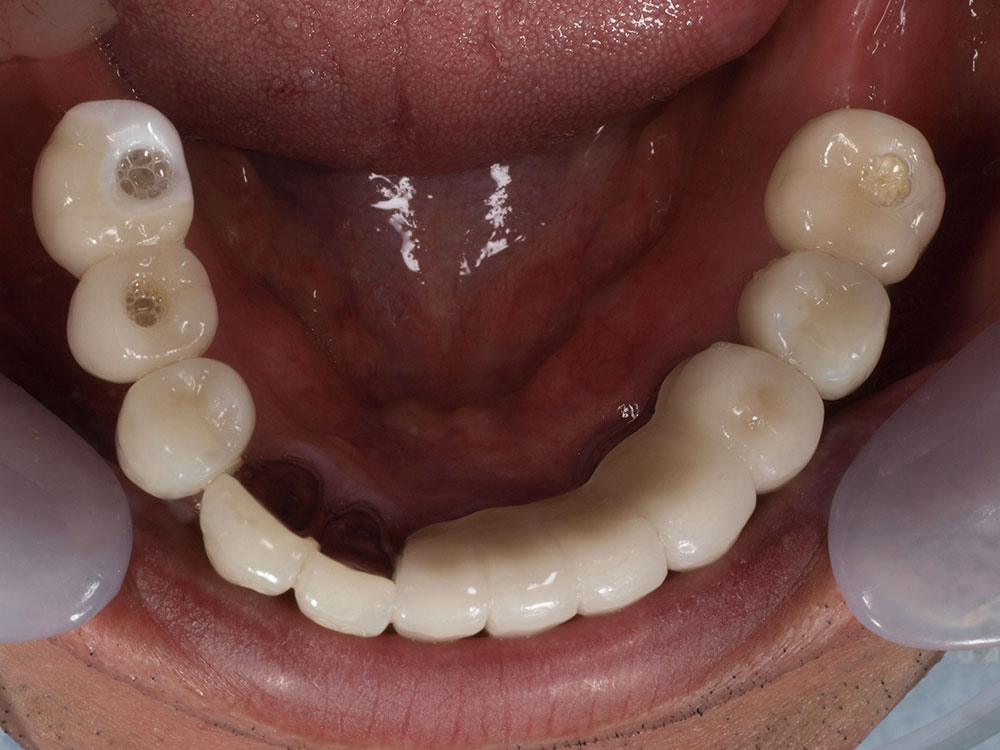

症例紹介

- 主訴

- 入れ歯が合わない。食べにくい。人生を豊かにしたい。

- 処置内容

- 上顎4本で12歯(オールオン4)、下顎4本5歯。

上下抜歯即時埋入、即時荷重(手術当日にインプラントの上に仮歯装着)

- 治療費用

- 上顎:約290万(税込)、下顎:約210万円(税込)

- 治療期間・通院回数

- 上顎:9か月/9回

下顎:6か月/7回

- リスク

- 術後の腫れ、痛み(ピークは3日後、1週間で軽減)

上部構造物、仮歯の破折、人工歯根脱落リスクがあります